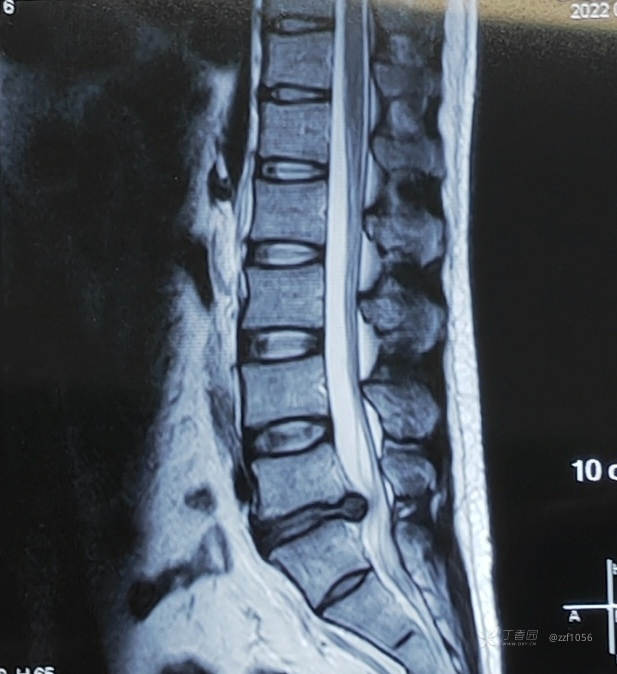

脱出明显

左侧,貌似两块

突出挤压行走根严重

减压后

很大一块